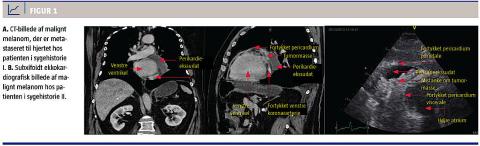

De cytologiske undersøgelser af PE viste metastasering af v-raf murine sarcoma viral oncogene homolog B1 (BRAF)-positivt MM. CT af thorax, abdomen og cerebrum viste ingen spredning fraset til perikardiet (Figur 1A). Man så ikke fornyet PE, men patienten fik vanskeligt behandlelig ventrikulær takykardi, multiple lungeembolier samt multiorgansvigt og afgik ved døden.

Patienten blev nogle måneder senere indlagt med hurtig atrieflimren og forværring af hjerteinsufficiens. Han havde gennem nogle måneder haft tiltagende dys- og ortopnø. En ekkokardiografi viste nu LVEF 5-10% samt et hæmodynamisk ubetydeligt PE og et malignitetssuspekt, ekkorigt epikardielt element (Figur 1B). Han blev frekvensreguleret og udskrevet i sin habituelle tilstand efter nogle dage. Han blev i efter udskrivelsen fulgt i onkologisk og kardiologisk ambulant regi med stationær sygdom.